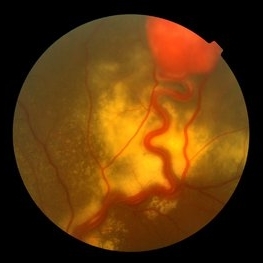

Behcet's Disease Behcet's DiseaseMar 13 2013 by Hamid Ahmadieh, MD Color fundus photograph of the right eye of a 23-year-old man with retinal vasculitis and branch retinal vein occlusion (BRVO) due to Behcet's disease . Photographer: Solmaz Shahmohammad, Negah Eye Center, Tehran Imaging device: Heidelberg Spectralis Condition/keywords: branch retinal vein occlusion (BRVO), retinal vasculitis